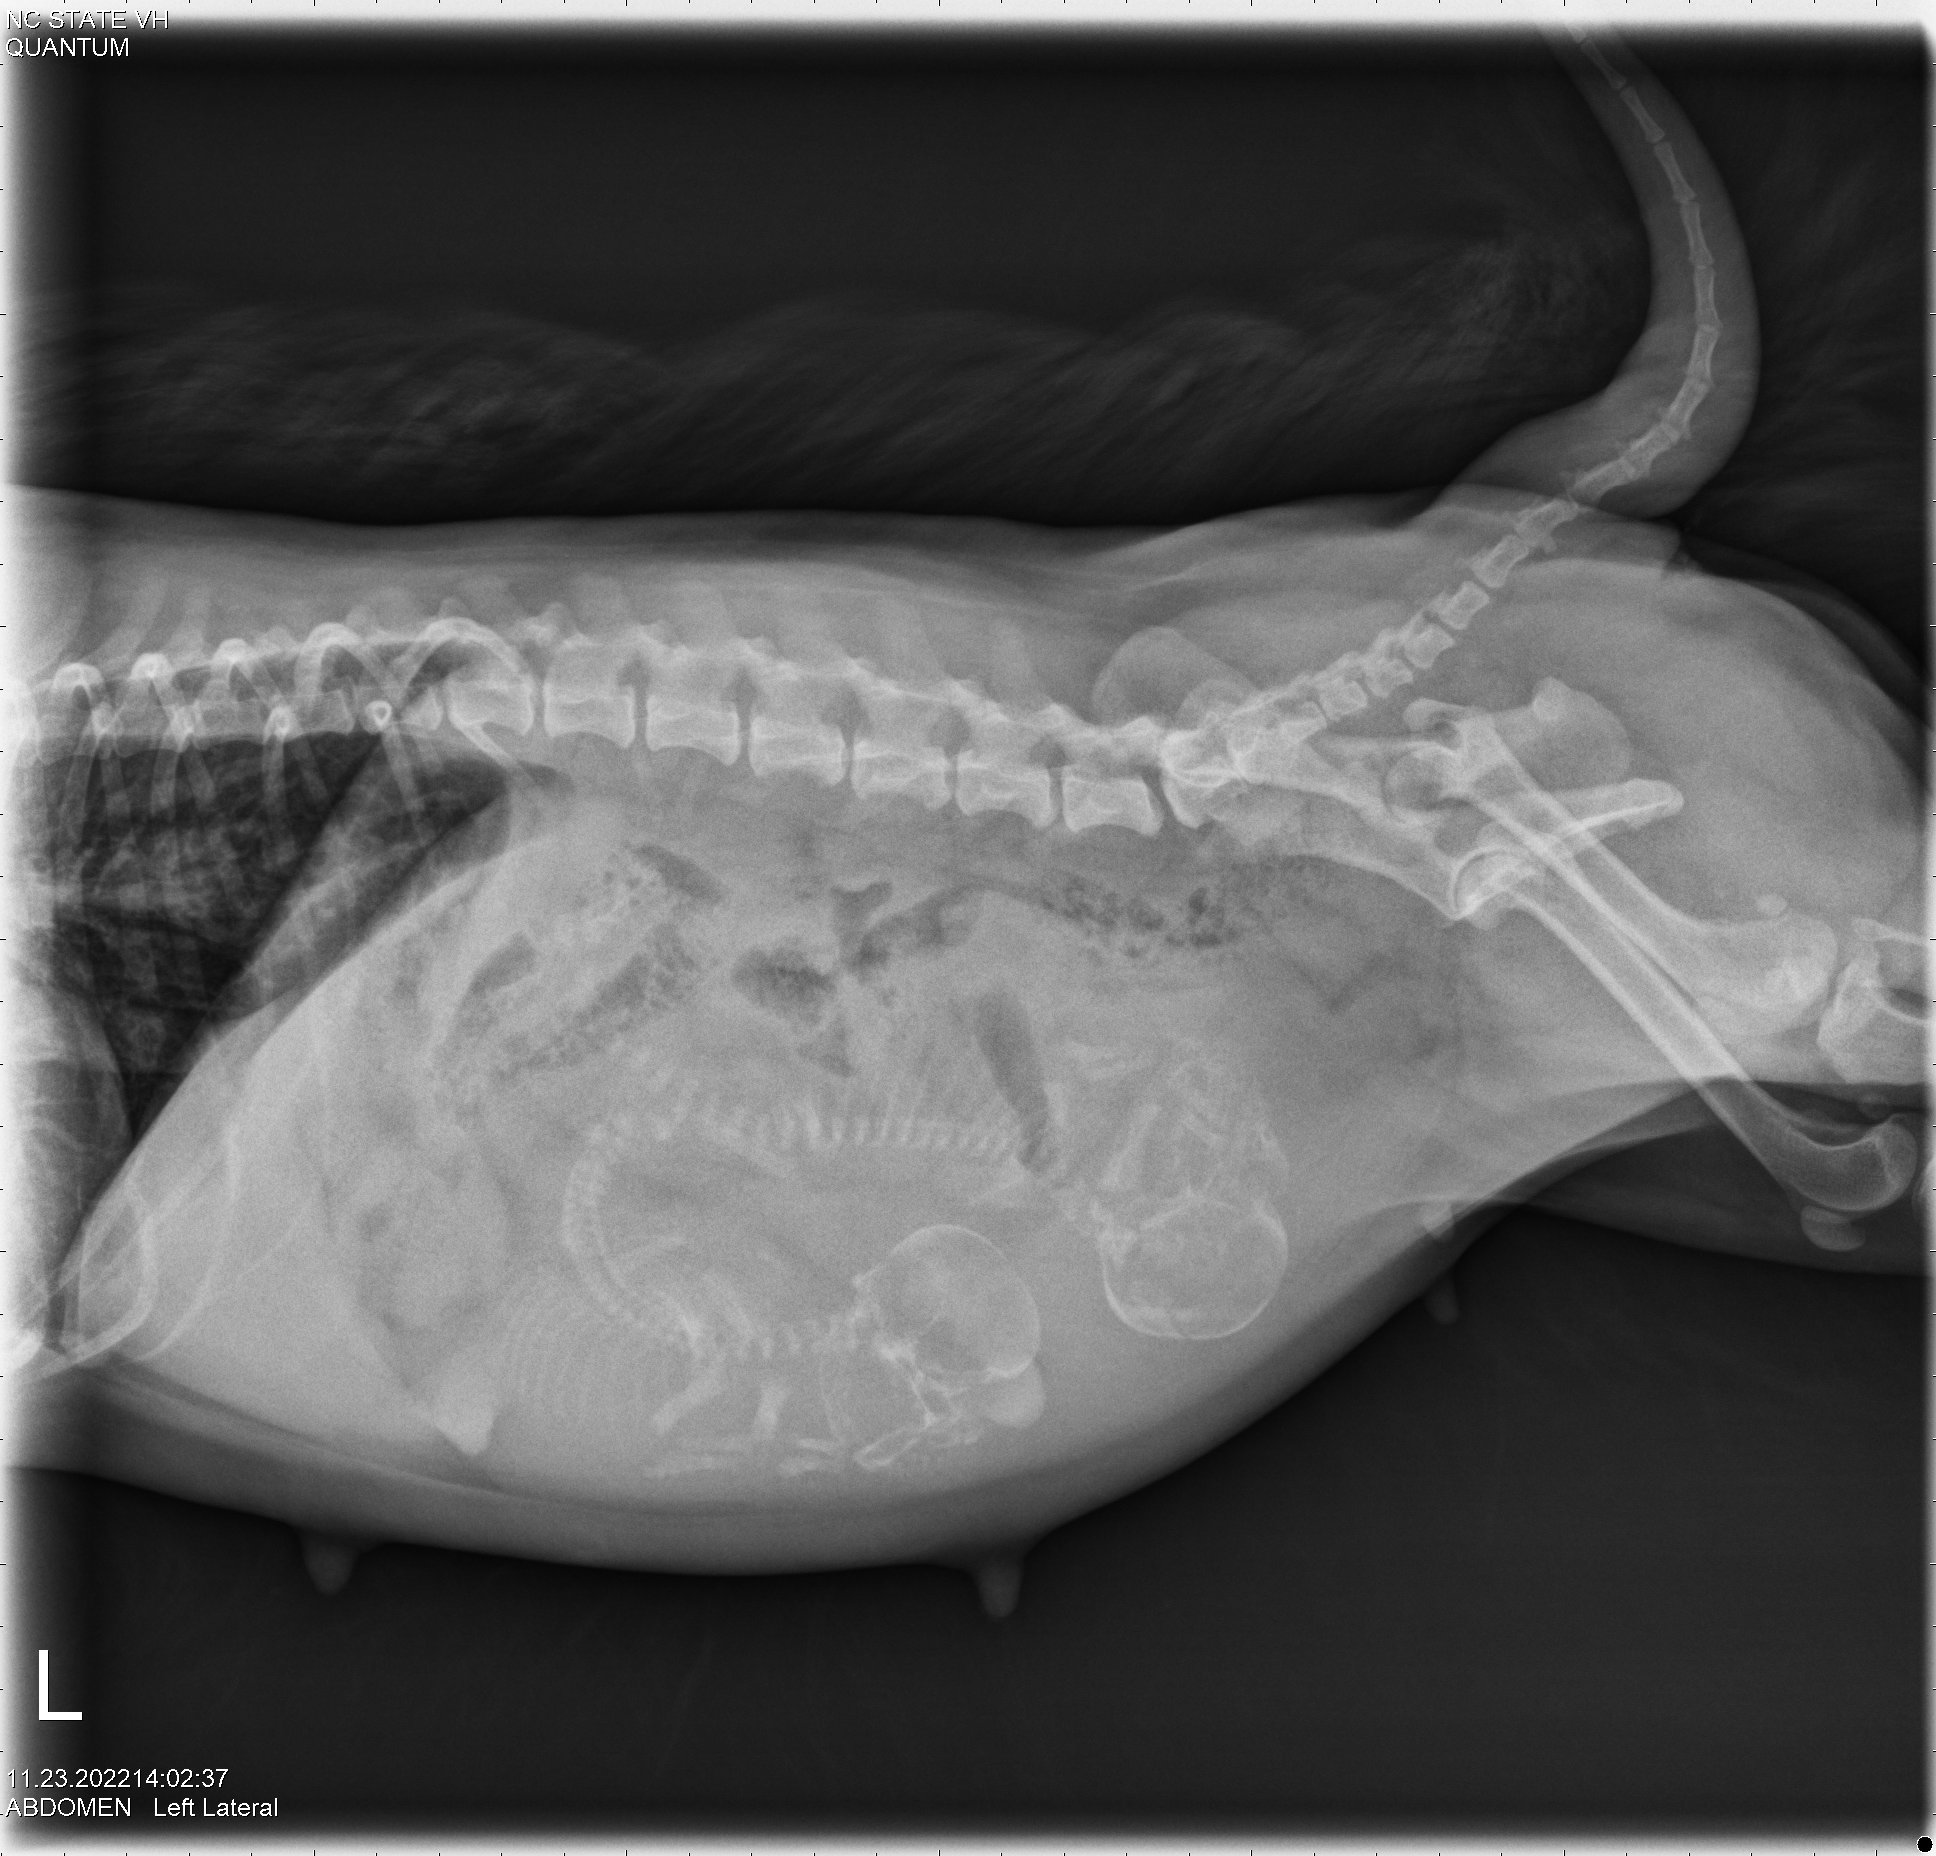

23 Nov

Since I was travelling, my petsitter was kind enough to take Siri to NC State for x-rays to count the number of puppies. The x-rays showed two puppies.

By measuring the size of the puppies' skulls and the width of Siri's pelvic opening, it was determined that the puppies should be able to fit through Siri's pelvis. Thus Siri might be able to have the puppies naturally (free-whelp), rather than needing a cesarean section (c-section). The rule of thumb is that if there is only one puppy, a c-section is almost always necessary; whereas if there are three or more puppies, one should try to free-whelp. If there are only two puppies, it is not clear what to do.